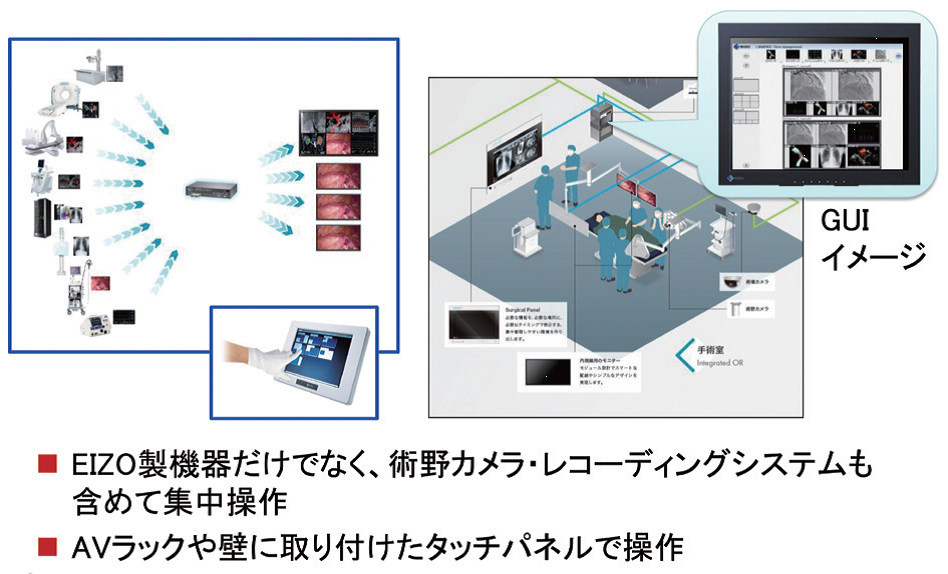

手術室の映像を集約・表示するシステム「CuratOR」

英単語curatorは、学芸員という意味で、美術館において設定されたテーマに応じて、最適な作品を選び展示する役割を担う。手術室におけるCuratORも同様に、手術の状況に応じて最適な映像を集約・表示する役割を担うもので、各スタッフへの最適な表示を実現する。

手術室内に分散する各映像を集約・表示するというアプローチで手術スタッフを支援する。

CuratORで使われる様々な機器の、シンプルかつ直感的な操作を可能にする。

CuratORの強みは、①各種映像信号の変換・集約、②映像を集約するための信号配信マネージャーの存在、③大型モニタの存在、である。

信号配信マネージャLMM(Large Monitor Manager)はCuratORの中心にあり、各種映像の集約・切り換えや、キーボード・マウスを共有するKVM機能、マウスやタッチパネルによる直感的なレイアウト切り換えを実現する。

ビデオコンバータは、手術室に存在する各種映像信号をLMMに入力できる形式に変換するもので、古くからある独特な信号を出力する医療機器にも対応する。

LMMの後段で複数の映像情報や生体情報を集約して表示する「Surgical Panel」は、壁に埋め込めるデザインで抗菌キーボード・マウスも付属。これまでカートで床置きしていた術中モニタや、PACSなどの医療機器の映像を集約することで、手術室内でのスタッフの移動・動線がすっきりする。KVM機能の活用で、患者の看護記録入力やPACS画像閲覧などの操作も集約可能。

これら機器を集中操作するソフトウェアは、必ずしもIT機器に詳しいとは限らない医療スタッフが直感的に全ての機器を操作できるよう設計されている(図2)。